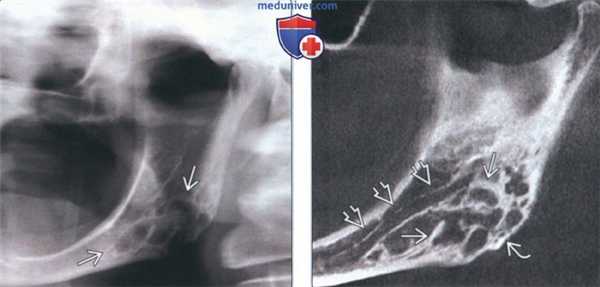

(Слева) На панорамной рентгенограмме определяется десмопластическая фиброма в виде многокамерного просветления в задних отделах нижней челюсти слева и в области угла. Отношение нижнечелюстного канала к опухоли неясно.

(Справа) На панорамной реформатированной КЛКТ у этого же пациента определяются толстые перегородки в опухоли, распространяющейся в нижнюю кортикальную пластинку. Отчетливо визуализируется смещенный кверху нижнечелюстной канал. Расположение опухоли под нижнечелюстным каналом позволяет исключить одонтогенное поражение.

2. Рентгенография при десмопластической фиброме челюсти:

• Интра- и экстраоральная рентгенография:

о Расхождение или резорбция корней

о Вздутие или перфорация кортикальной пластинки (29% случаев)

о Иногда может обнаруживаться лучистая периостальная реакция, имитирующая остеогенную саркому

о Может наблюдаться смещение нижнечелюстного канала

3. КТ при десмопластической фиброме челюсти:

• КЛКТ и КТ в костном окне:

о Позволяют лучше оценить многокамерную структуру, кортикальные эрозии, периостальную реакцию